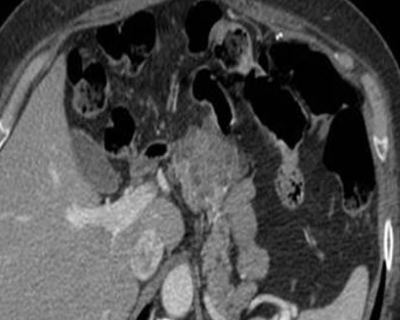

Cystadénome Séreux

- Bénin SANS risque de transformation

- Masse microkystique plutot grande >2cm

- Tête du pancréas++

- PAS de capsule

- Calcifications plutot centrales

- Vu dans le VHL

- Grandma lesion